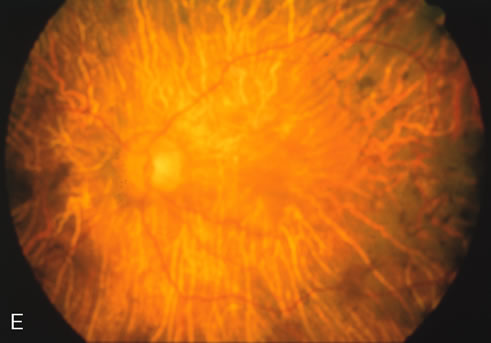

Fig. 2. Golden tapetal reflexes. There are three diseases in which there is an unusual golden reflex to the fundus: X-linked recessive RP in the carrier female, Oguchi's disease, and cone dystrophy. In all these diseases the angiogram is essentially normal, suggesting that this reflex is probably not related to pigment abnormalities. A, B. Carrier female of XLR retinitis pigmentosa. A golden scintillating reflex radiates from the macula. C, D. Oguchi's disease. A diffuse yellow metallic sheen is seen in the posterior pole (a pigmented chorioretinal lesion is an incidental finding). E, F. Progressive cone dystrophy. The typical bull's eye maculopathy is associated with a golden orange reflex.

In Oguchi's disease the hallmark fundus finding is a yellow metallic sheen (Fig. 2C). A similar sheen has been seen in progressive cone dystrophies and juvenile macular degeneration.7 In all these diseases the abnormal reflex does not affect the normal transmission of fluorescein dye (Fig. 2D). The normal FA suggests that, like findings in the carrier female in XLR RP, the abnormal retinal reflex in this disease is unrelated to pigment concentration or distribution.

Fluorescein angiography highlights observable fundus findings. In patients with a golden reflex the FA is normal (Fig. 2E, F) or shows a mild transmission hyperfluorescence.7